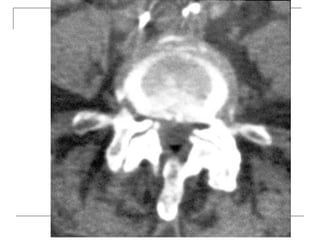

CT Scan

 better visualization of bone pathology (eg.

cortical destruction)

 fracture

 tumor